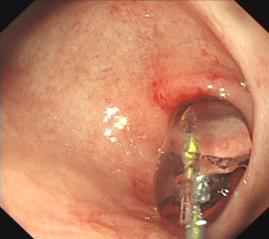

1. 内镜下止血术:采用内镜下微创治疗方法,有效止血,成功率达95%以上;凡来我院的消化道出血病人昼夜24小时内均可得到急诊胃肠镜的及时诊治,使消化道出血病人的死亡率、并发症及诊治费用均大幅降低;

胃底溃疡并出血止血术